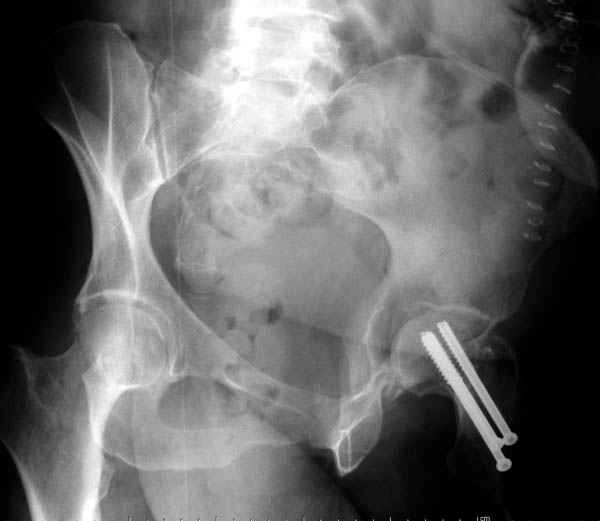

На картинке подобный случай, только без шейки, сделано через месяц или полтора после травмы.

В положении на спине подвздошным и надлобковым доступом восстанавливается тазовое кольцо, фиксация пластинами. При хорошей репозиции может улучшиться конгруэнтность в суставе.

Затем, если положение хорошее, закрытый остеосинтез шейки винтами.

Если нет - в положении на боку, синтез задней колонны из наружно-латерального доступа и синтез головки винтами, но уже под визуальным контролем.